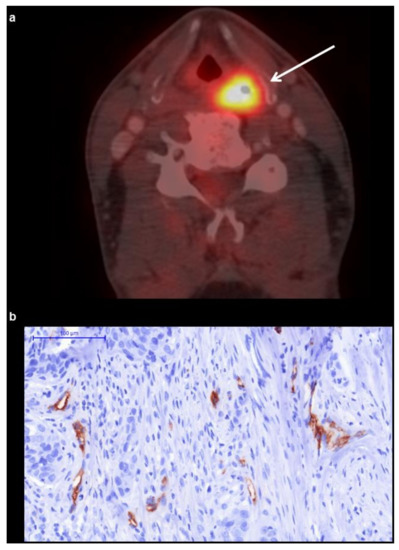

18F-FDG-PET/CT

2.3. Microvessel Density